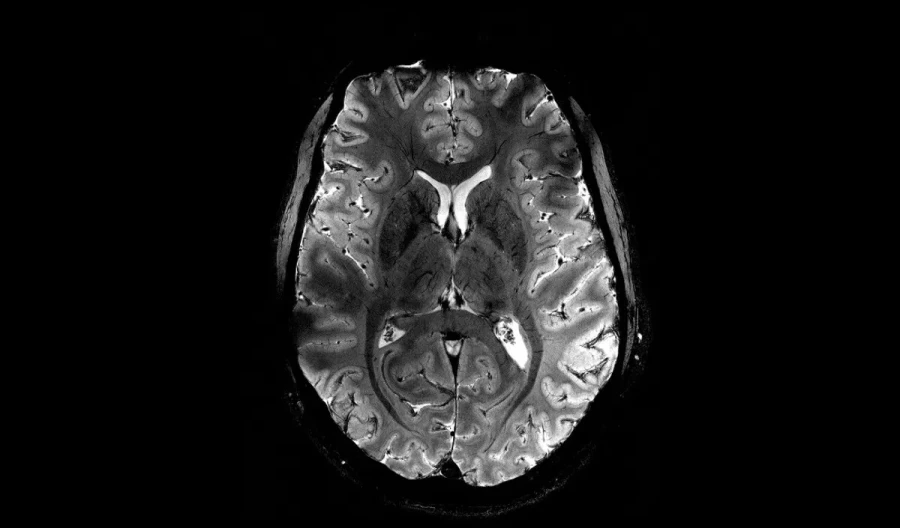

Αλλά πέρα από την ωμή ταχύτητα της διαδικασίας, η ανάλυση που προσφέρει ο σαρωτής μαγνητικής τομογραφίας Iseult μπορεί να επιτρέψει στους επιστήμονες να μελετήσουν υγιείς και άρρωστους εγκεφάλους σε ζωντανούς ανθρώπους με πολύ πιο υψηλό επίπεδο λεπτομέρειας απ’ ό,τι είχε η επιστήμη στα χέρια της μέχρι σήμερα.

Στο πεδίο έρευνας για το Αλτσχάιμερ και το Πάρκινσον, για παράδειγμα, αυτή η διαφορά θα μπορούσε να παρέχει νέες πληροφορίες για τον νευροεκφυλισμό που συμβαίνει σε διαφορετικές περιοχές του εγκεφάλου και να βοηθήσει στη βελτίωση της διάγνωσης και της θεραπείας.

Η χρήση μιας έντασης πεδίου αυτού του μεγέθους επιτρέπει επίσης στον σαρωτή να λαμβάνει ορισμένα χημικά σήματα που δεν μπορούν να ανιχνευθούν με τους συμβατικούς σαρωτές. Ένα από αυτά είναι το λίθιο, ένα φάρμακο που μερικές φορές χρησιμοποιείται στη θεραπεία της διπολικής διαταραχής. Με αυτόν τον σαρωτή, οι επιστήμονες θα μπορούν να δουν πώς κατανέμεται το λίθιο στον εγκέφαλο, για να κατανοήσουν καλύτερα πώς λειτουργεί.